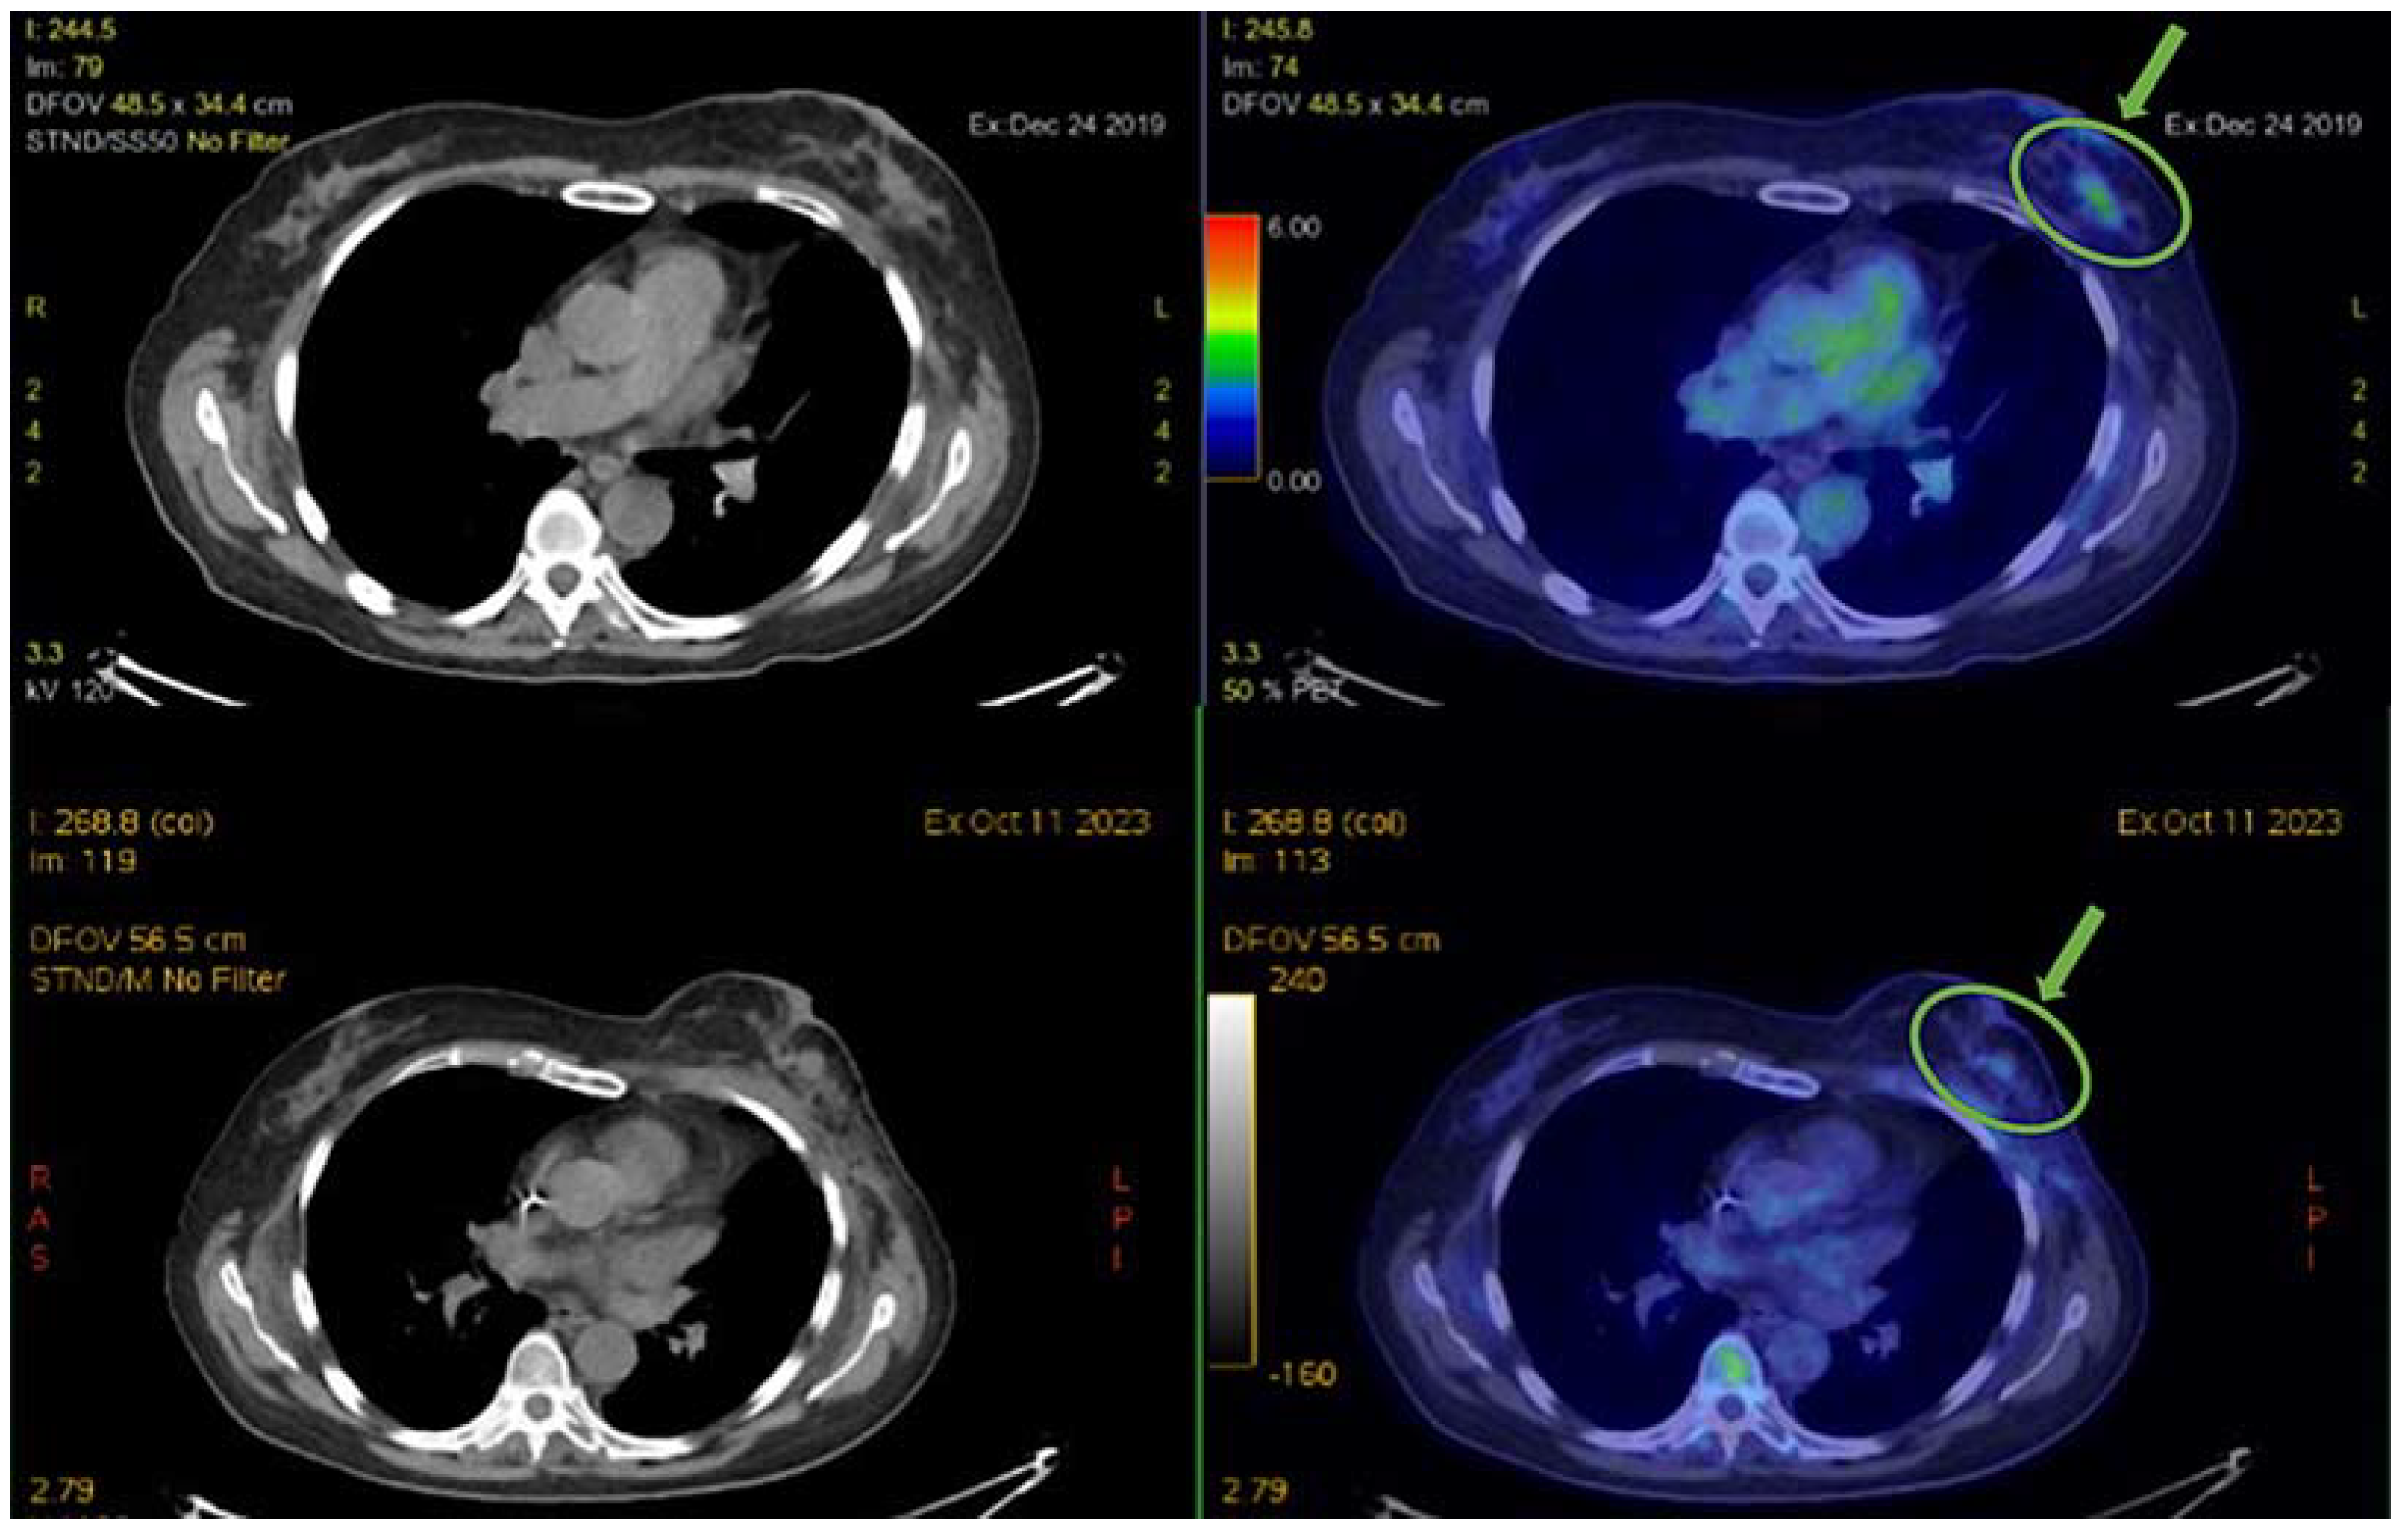

After 8 years, in 2019, a recurrence of skin nodules at the site of previous breast surgery was diagnosed. A biopsy showed a significant change in the biology of the disease, with the loss of hormone receptor expression (ER/PgR 0/0%), while HER2 remained negative, and the level of Ki-67 was 25%. The systemic staging of the disease with an 18-18F-fluorodeoxyglucose (FDG)—positron emission tomography (PET) scan showed a weak uptake at the level of the known skin nodules and bilateral axillary lymph nodes (the top of the image of Figure 2).

Figure 2.

PET scan analysis before and after prolonged treatment. Top: 2019 PET scans; bottom: 2023 PET scans. The green arrow indicates the captured tracer and the ROI points to the region showing substantial disease control after 4 years.

FDG-PET was performed to diagnose the patient’s breast cancer and then, during first-line mCHT and subsequent MTD chemotherapy, to follow the tumor’s response to therapy. A comparative analysis of the patient’s 2019 and 2023 PET images shows substantial stability/slight reduction of disease over a period of 4 years, from the diagnosis of metastatic disease to the present, highlighting the excellent control of the systemic disease obtained with the sequence of treatments carried out, as indicated by the green arrows and the ROI (region of interest) in Figure 2.